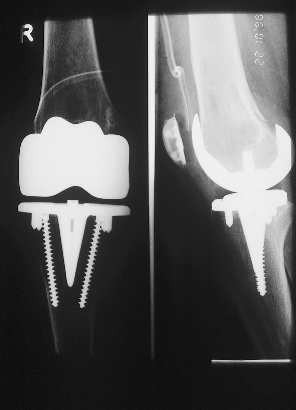

Example of a complete prosthesis

Left: Here an existing, elsewhere placed prosthesis was changed because of loosening, and due to bone loss the height had to built up on the shin.

Center left and center right: A modern knee prosthesis with sparing bone removal and sliding surface replacement. Such knee joints are used routinely by us. They are made for the particular patients affected knee.

Right: A so-called "total femur": A solution for desperate cases, in which there is no other way to preserve the limb: The hip (left) and knee (center and right) had to be completely replaced in a session. The anchorage is deep into the lower leg. The hip and knee part are strongly connected through the femur. It is a so-called tumor prosthesis.